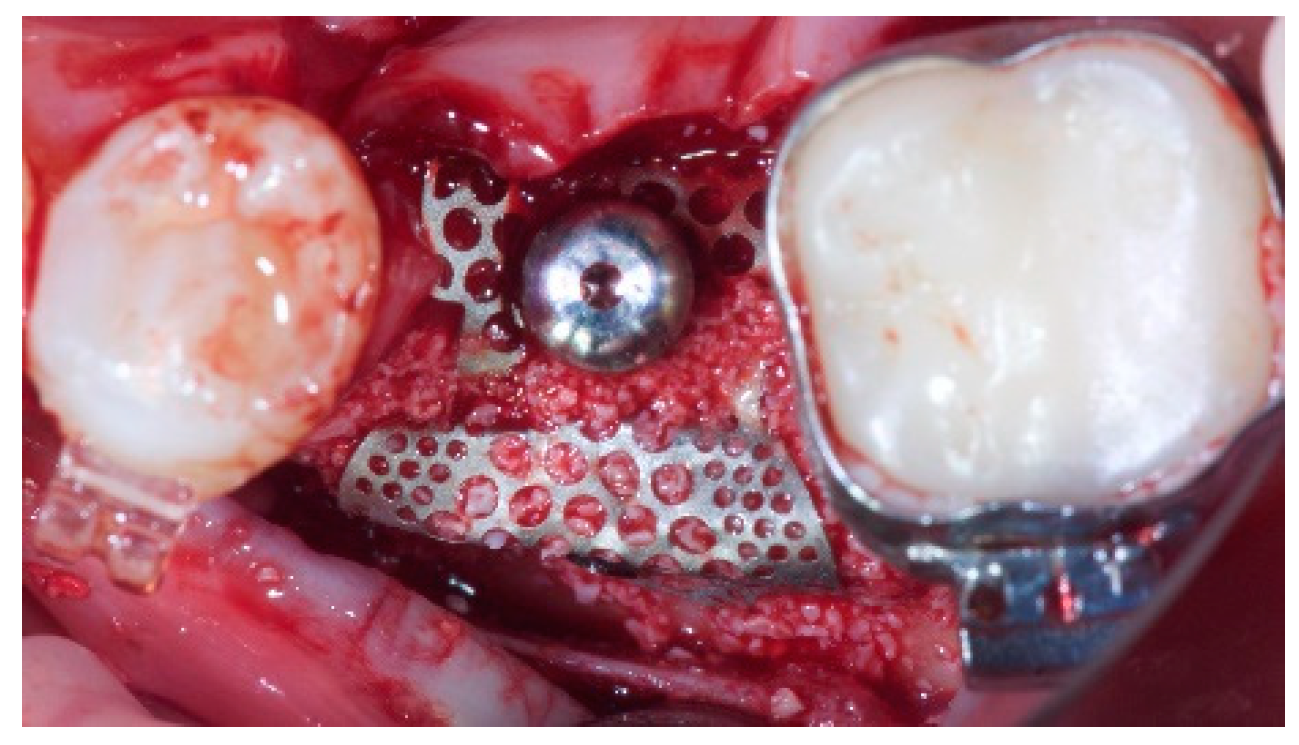

2. Materials and Methods

- Horizontal bone augmentation was evaluated at the CBCT scans, 1 mm below the original bone crest. The volumetric data were superimposed using the adjacent teeth as reference points, and a new generated set of DICOM data was stored as a separately files. Measures were taken before and after the treatment, and the difference of these two measurements was taken as horizontal bone augmentation (Figure 9).